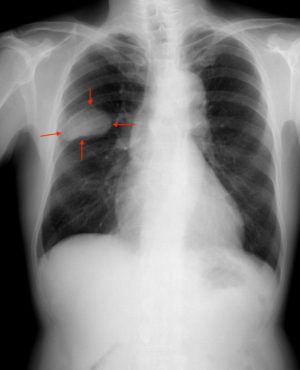

右肺S2-3の小細胞癌。

肺がんとは、肺から発生したがんの総称です。

特に高齢の男性では、がんのなかでも最も発生頻度が高く、日本では第1位です。肺がんには、顕微鏡でみたがんの組織の特徴から、腺がん、扁平上皮(へんぺいじょうひ)がん、大細胞がん、小細胞がんなどの種類がありますが、臨床的には、その治療方法の違いから、小細胞がん、非小細胞がんと大きく2つに区別しています。今後ますます高齢化社会が進むことによって増加する病気であることは間違いありません。最も重要なことは、他のがんと同じで早期発見、早期治療です。非小細胞がんで、早く見つかり治療をすれば5年生存率は50~70%ですが、肺内のリンパ節に転移した場合、5年生存率は30~50%に下がってしまいます。肺がんは進行が早く、転移もしやすいため、安らかな晩年の生活を大きく阻害する原因になります。特に、ヘビースモーカーの高齢男性には、要注意の病気です。